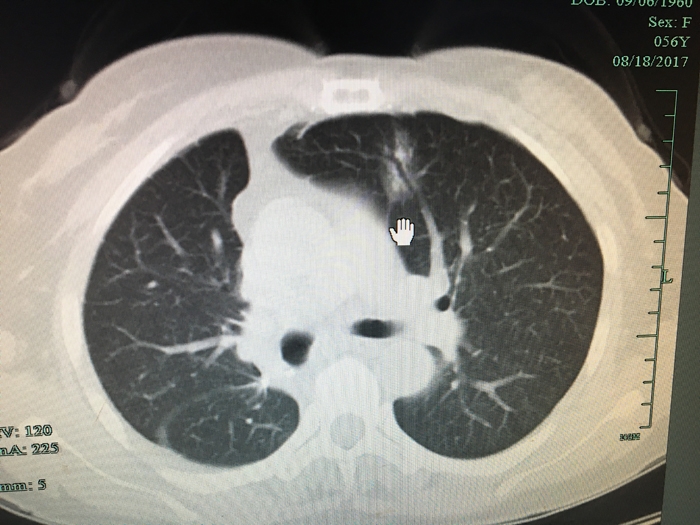

??? 三個(gè)多月前,市區(qū)的劉阿姨因?yàn)樾夭坎贿m來(lái)到我院就診。經(jīng)過(guò)CT檢查發(fā)現(xiàn)右下肺及左上肺各有一枚結(jié)節(jié),家人知道后非常著急,找到了心胸外科團(tuán)隊(duì)。

術(shù)前CT

??? 劉阿姨50多歲,平時(shí)體質(zhì)偏弱,考慮到劉阿姨兩肺結(jié)節(jié)均為惡性腫瘤,呂定量主任醫(yī)師團(tuán)隊(duì)進(jìn)行會(huì)診討論,雙側(cè)同時(shí)手術(shù)會(huì)明顯增加患者的手術(shù)風(fēng)險(xiǎn),決定先處理右側(cè)較大的病灶,3個(gè)月后待體質(zhì)恢復(fù)后再處理左上肺小病灶。主管醫(yī)生萬(wàn)海軍為了減少劉阿姨的創(chuàng)傷,進(jìn)行了單孔胸腔鏡下右下肺癌根治術(shù)的微創(chuàng)治療,手術(shù)過(guò)程很順利,術(shù)后病理報(bào)告證實(shí)為:浸潤(rùn)性腺癌,劉阿姨術(shù)后也恢復(fù)得很好。